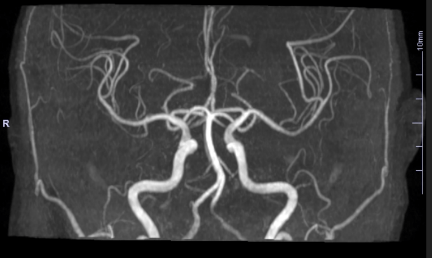

MRI(Magnetic Resonance Imaging):磁気共鳴画像の略です。 磁石の大きなトンネルの中に体を入れて、磁力と電磁波を用いて身体の断面画像を作ることができる画像診断装置です。

CTと同様の体の断層像が得られますが、CTでは厚い骨に囲まれた骨髄、椎間板、頭部一部、関節は不得意な部分もありますが、MRIは脊髄や脳の細かな情報を得ることができます。

当院のMRIは高磁場でより優れた画像を得ることができます。例えば、急性の脳梗塞では、症状が出現してからの数時間はCTでは病変がでないことがありますが、拡散強調像という操作で描出することが可能です。

MRIの拡散強調像による発症後間もない急性期の脳梗塞巣